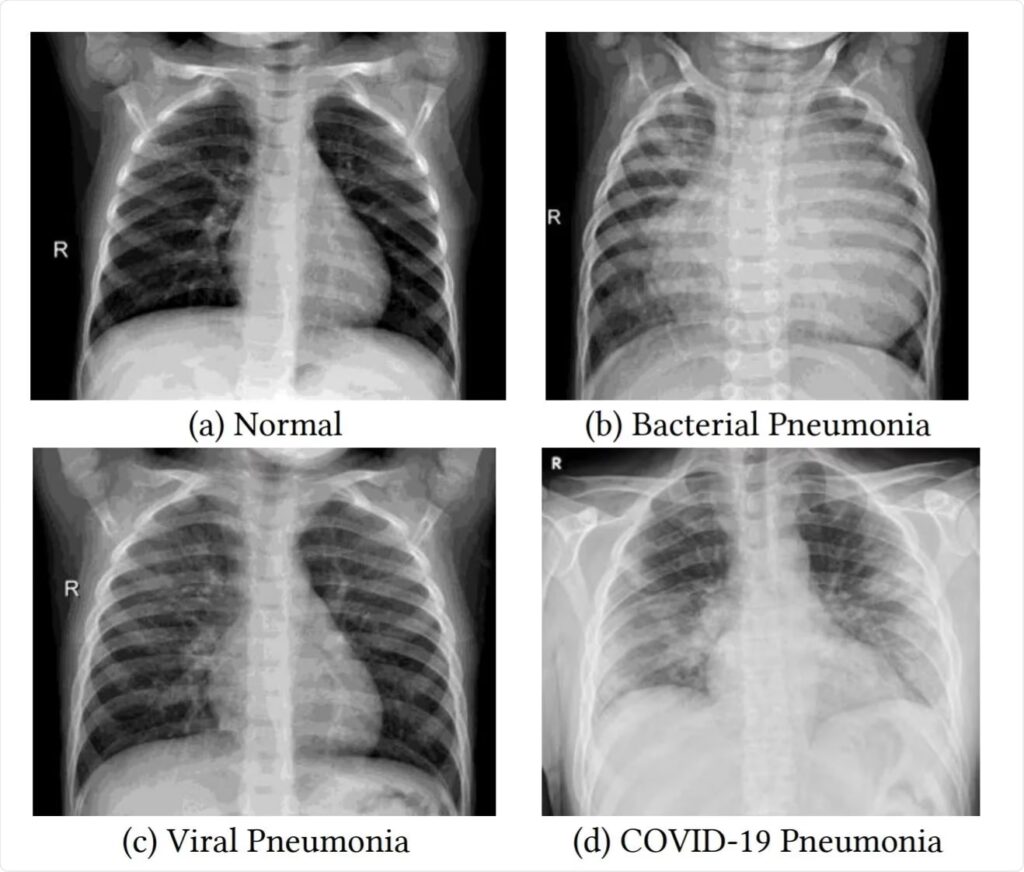

På et normalt røntgenbillede af brystkassen fremstår lungerne som mørke områder, fordi de primært er fyldt med luft, som røntgenstråler let passerer igennem. Knogler, som brystben og ribben, samt hjertet, fremstår hvide eller lysegrå, fordi de er tættere og absorberer mere stråling.

Når en person har lungebetændelse, bliver de små luftsække i lungerne (alveolerne) fyldt med væske, pus og inflammatoriske celler. Denne ansamling af væske og celler gør lungevævet tættere. På et røntgenbillede vil disse tættere områder fremstå som hvidlige eller uklare pletter, kendt som infiltrater eller fortætninger. Udseendet af disse fortætninger kan variere meget afhængigt af typen og sværhedsgraden af lungebetændelsen.

Forskellige Typer af Lungebetændelse og Deres Udseende

Afhængigt af årsagen og spredningsmønsteret kan lungebetændelse præsentere sig forskelligt:

3. Interstitiel Lungebetændelse

Denne type påvirker interstitiet – det fine bindevæv, der omgiver luftsækkene. På billedet ses et diffust, net-lignende (retikulært) mønster i stedet for tætte fortætninger. Dette mønster kan ligne lungefibrose og er ofte forårsaget af vira eller atypiske bakterier som Mycoplasma pneumoniae.